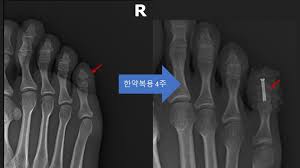

또한, 복합 골절이나 압박 골절과 같이 더 복잡한 경우에는 수술이 필요할 수 있으며, 뼈가 조각나거나 비스듬하게 부러진 경우에는 금속판을 추가적으로 사용할 수 있습니다.

- 수술 후: 수술을 받은 경우, 수술 후에는 추가적으로 2~4주 동안의 치료가 필요할 수 있습니다.